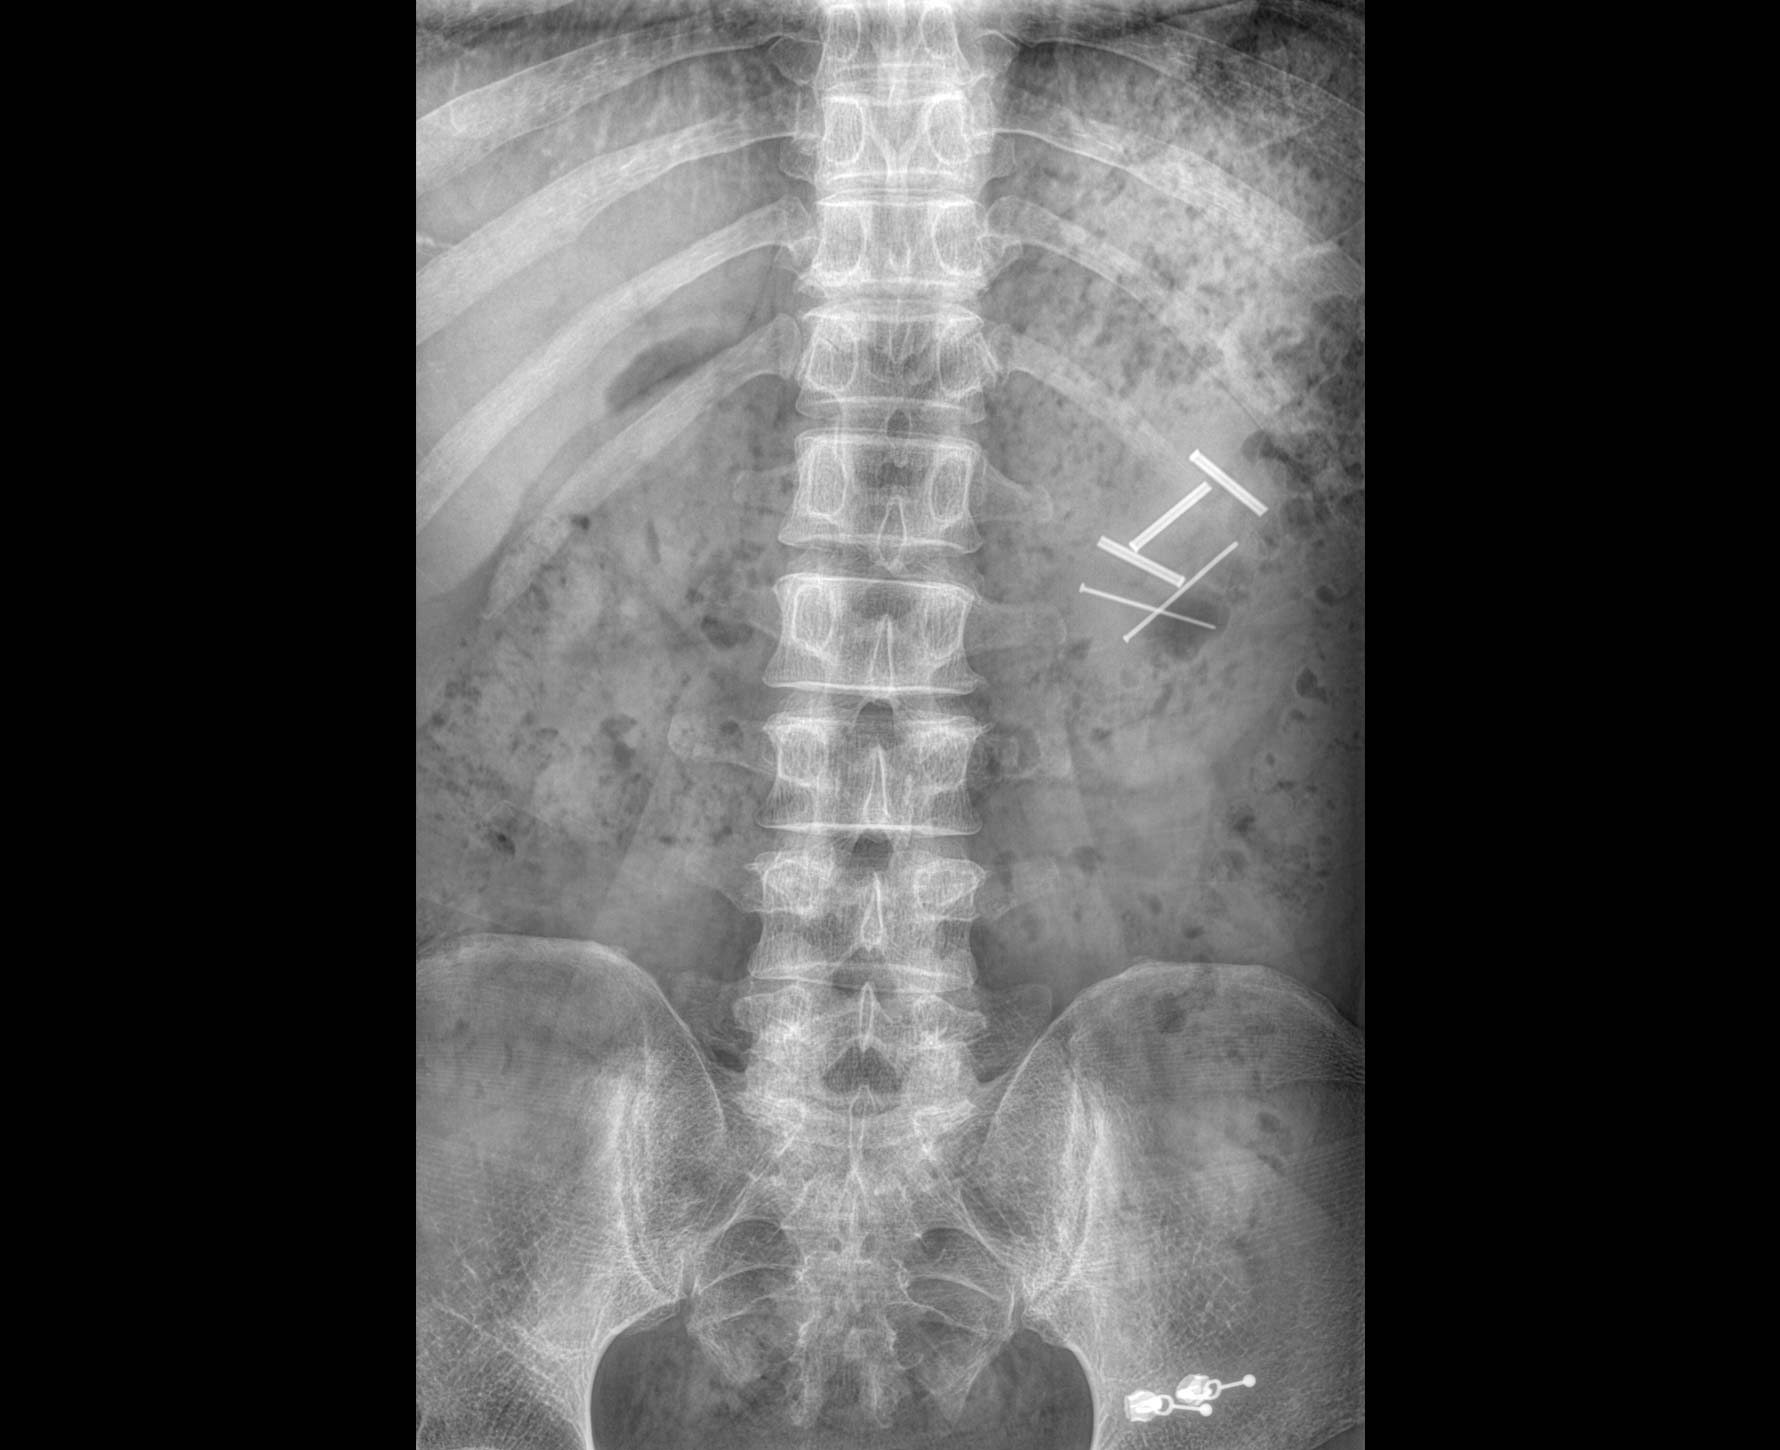

临床图像